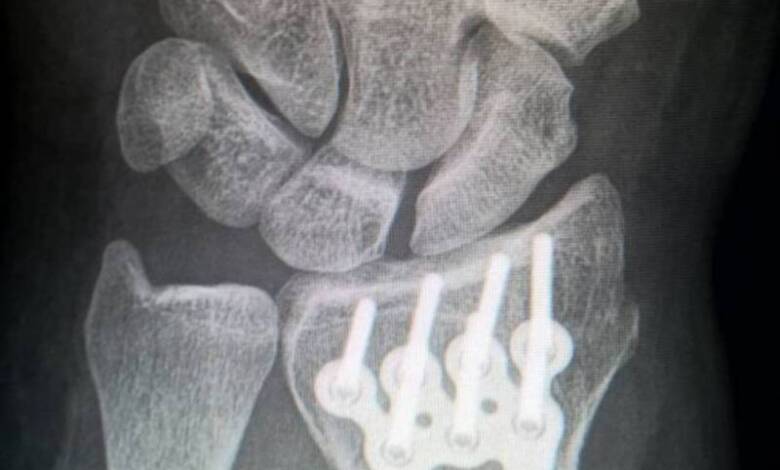

La osteogénesis imperfecta (OI) es una enfermedad genética rara que provoca huesos extremadamente frágiles, lo que lleva a fracturas frecuentes y deformidades óseas. Sin embargo, un reciente ensayo clínico realizado en el Hospital Universitario Karolinska, en Suecia, reveló un tratamiento que podría transformar la forma en que se maneja esta condición.

El estudio demostró que la terapia con células madre mesenquimatosas redujo hasta un 78% los episodios de fractura en los pacientes pediátricos. Estas células, que tienen una alta capacidad para generar tejido óseo, fueron administradas tanto de forma prenatal como posnatal, en un enfoque multidisciplinario sin precedentes en la medicina actual. En la segunda evaluación anual, más de la mitad de los niños tratados no sufrió fracturas, un hallazgo sorprendente que marca un hito en el tratamiento de la OI.

Los resultados del estudio BOOSTB4 ofrecen un cambio significativo en el tratamiento de la osteogénesis imperfecta. Mientras que las terapias tradicionales, como el uso de bisfosfonatos y la rehabilitación, solo alivian parcialmente los síntomas, la terapia celular actúa directamente sobre la formación de hueso y reduce la frecuencia de fracturas.

En la segunda evaluación anual, más de la mitad de los pacientes no experimentó nuevas fracturas, mientras que en el resto, el número de fracturas disminuyó significativamente.